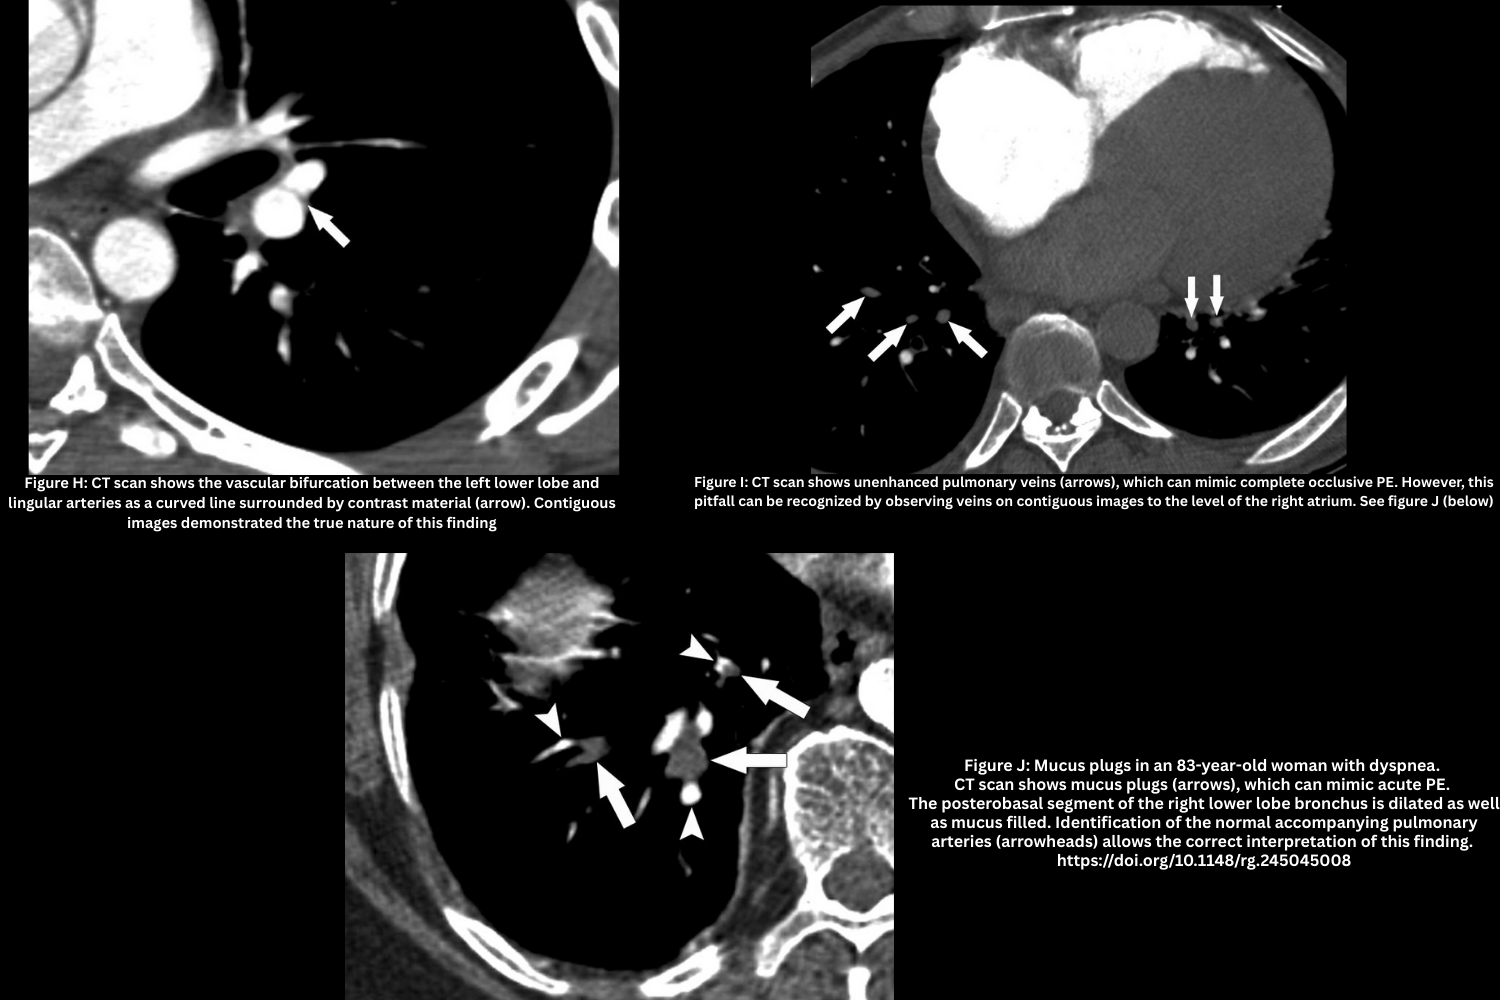

- Vascular bifurcation (Figure H).

- On axial images, vascular bifurcations may simulate linear filling defects

- Confirm with multiplanar reformats (Sagittal and coronal images can help identify these normal anatomic structures).

- Vein misidentification (Figure I).

- Unopacified pulmonary veins may be mistaken for arteries with a clot.

- Trace vessels to the left atrium to confirm venous anatomy.

- Mucus plug (Figure J, above).

- Dilated, mucus-filled bronchus mistaken for intravascular thrombus.

- Normal contrast-filled artery adjacent helps differentiate.